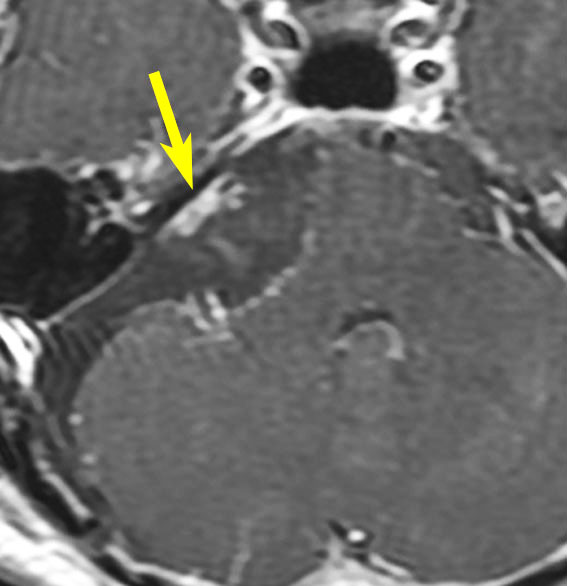

腫瘍の部分摘出です。手術翌日のMRIです。黄色の矢印の先に白く写っているのがごくわずかな残存腫瘍で,厚さ数mmくらいです。なぜこの部位だけ残すかというと顔面神経がペラペラになっていて腫瘍が外せないからです。このくらい取れると放射線治療を加えないで経過観察します。大きな塊が残ってしまうような部分摘出ではだめです。